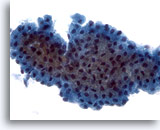

Figure 85

Parotid FNA, Warthin tumor (adenolymphoma).

Lymphocytes are admixed with oxyphilic cells in a background of amorphous debris. 95% of Warthin tumors occur in the parotid gland. 40x

Parotid FNA, Warthin tumor (adenolymphoma).

Lymphocytes are admixed with oxyphilic cells in a background of amorphous debris. 95% of Warthin tumors occur in the parotid gland.

40x